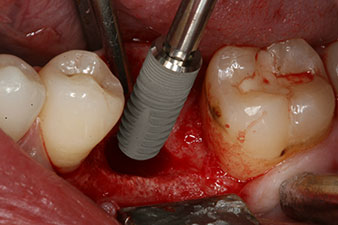

The implant was placed as planned after thorough removal of the granulation tissue (blueSky, bredent).

The torque used for the machine-driven placement was 43 Ncm. In addition, after screwing a measuring post (SmartPeg) specially matched to the implant, the ISQ value was measured with the probe of the W&H Osstell ISQ module.

This module is an optional extra for the W&H Implantmed and is docked to the implantology motor (see Fig. 11). The dimensionless ISQ value immediately after insertion was 64 orovestibular and 68 mesiodistal (maximum value = 100).

These values could have indicated open healing or even immediate restoration. Due to the insufficient crestal bone volume at the implant, the region was augmented with the bone chips collected during preparation of the implant bed and sutured to exclude saliva.